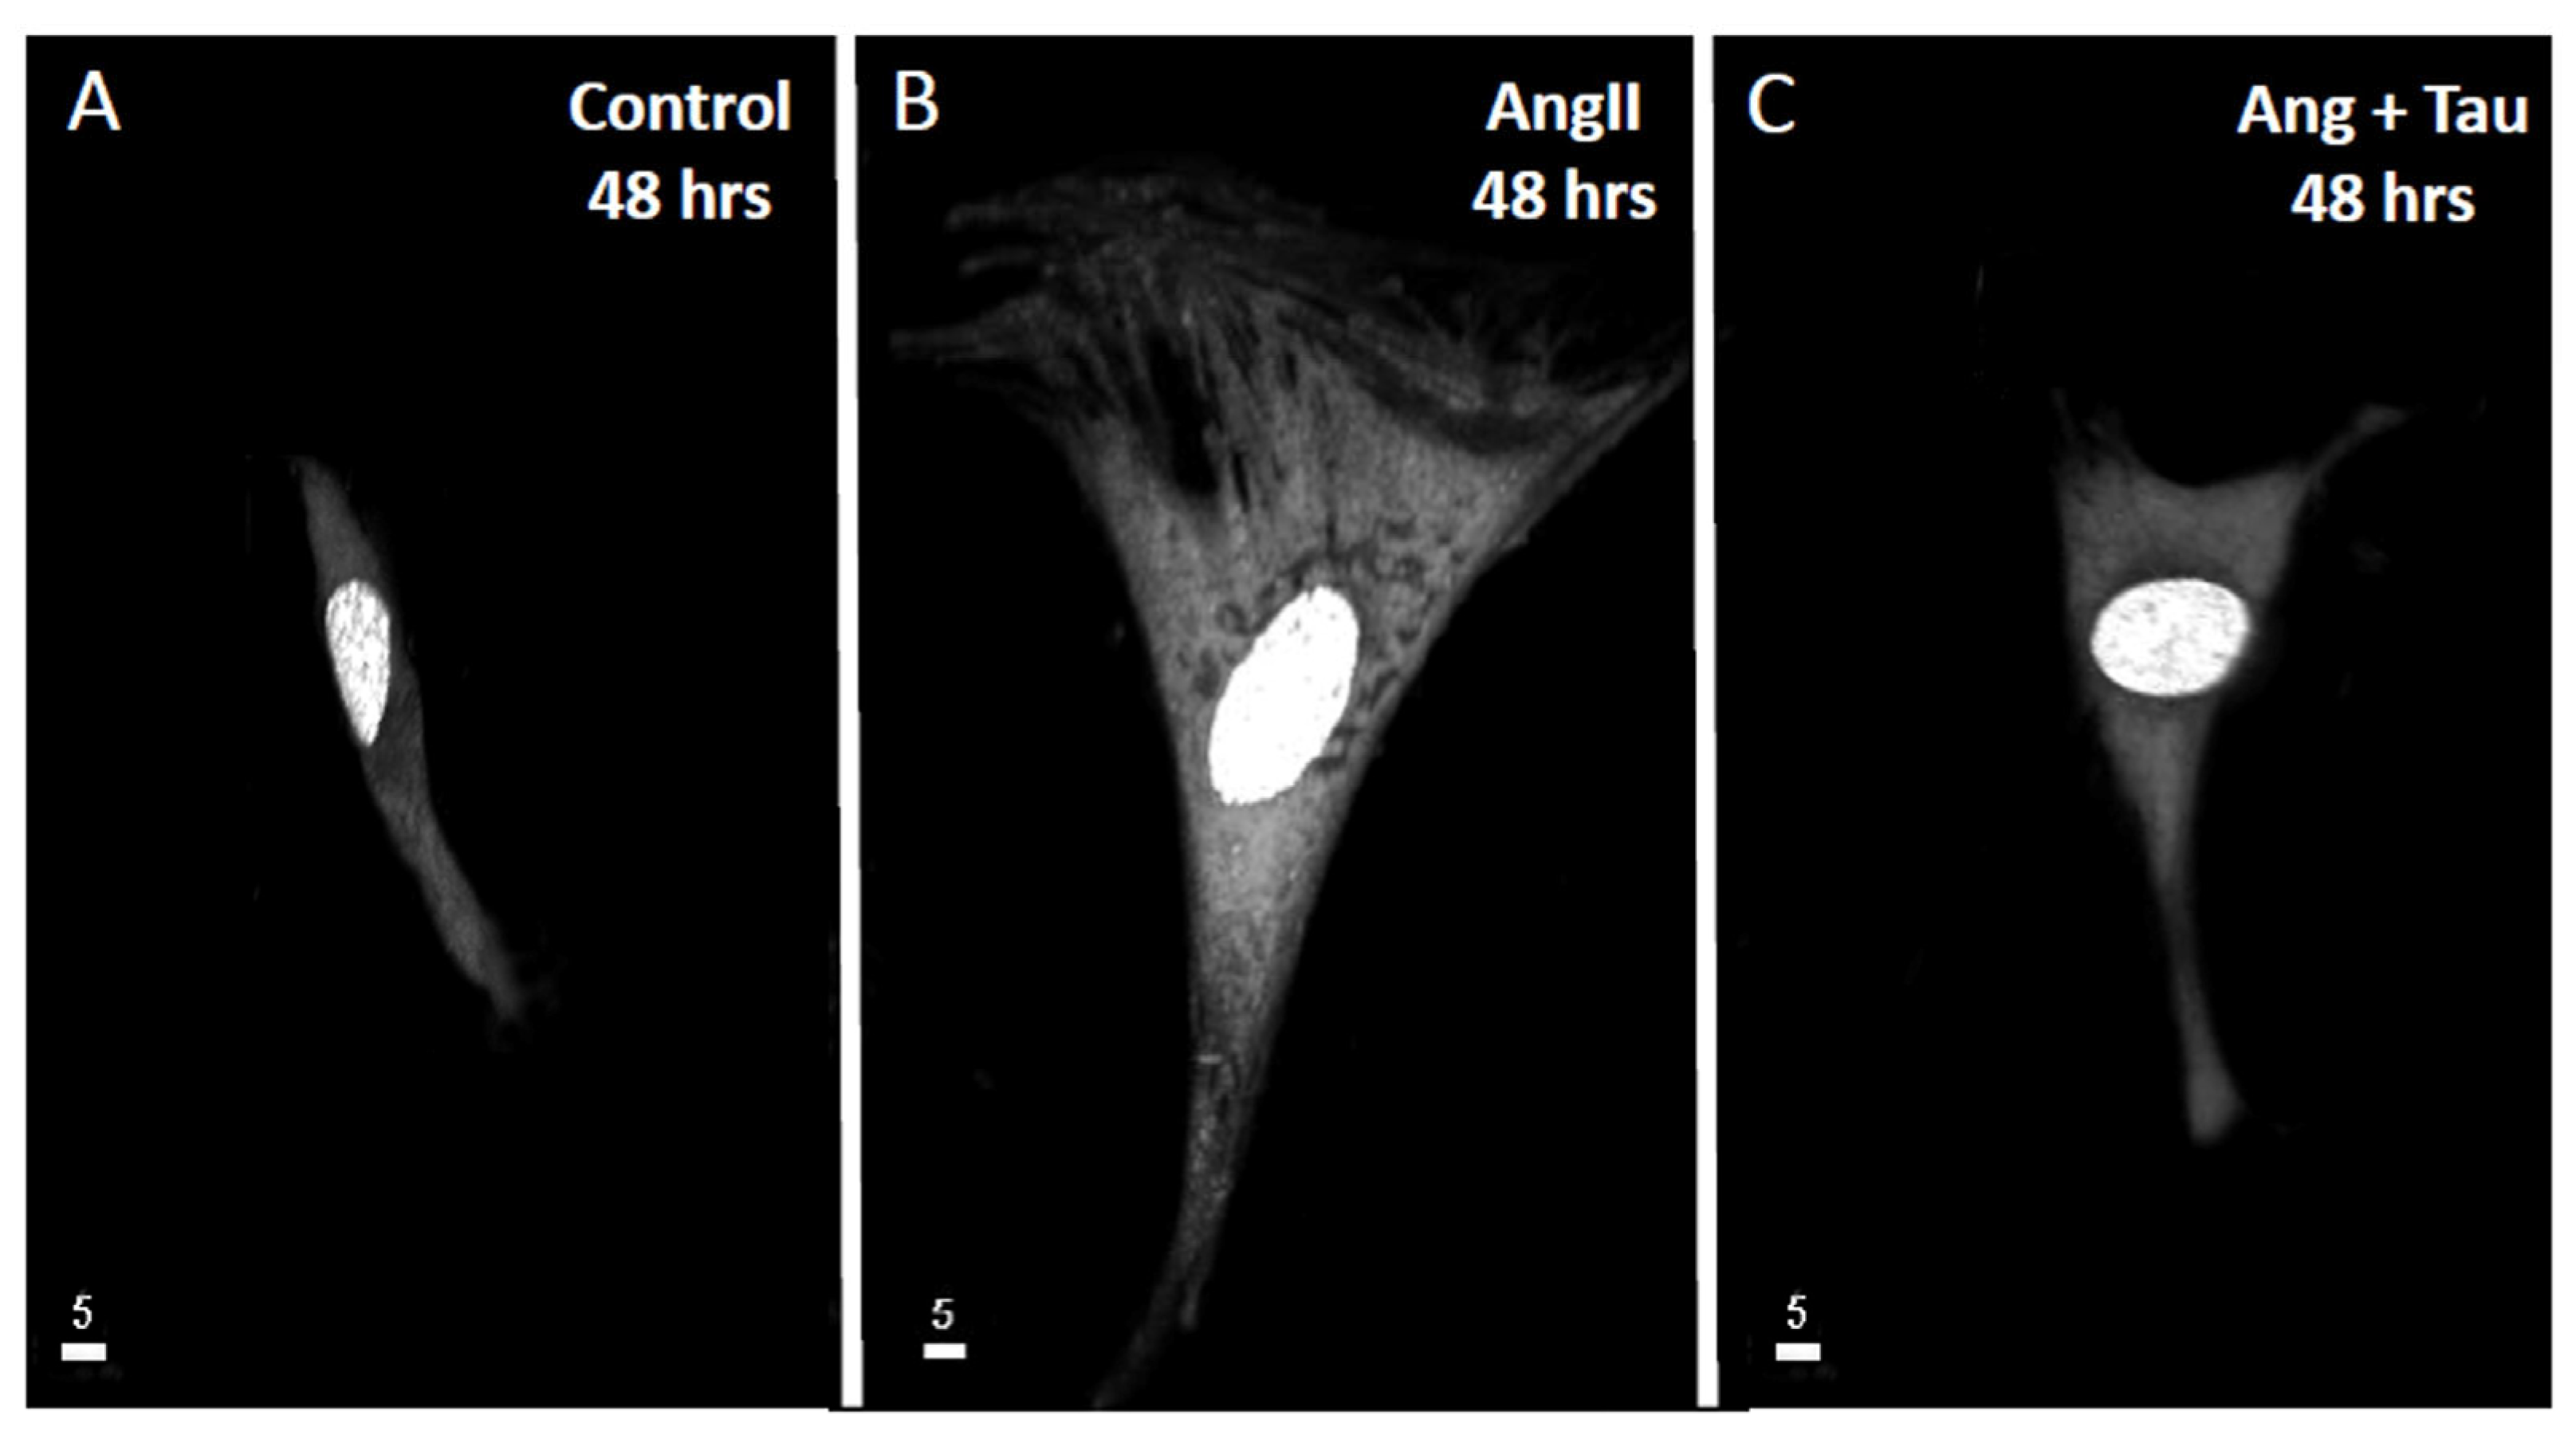

To verify if Ang II induces hypertrophy of hEECs, the cells were exposed for 48 h to 10−7 M of Ang II. Our group reported that this concentration increased intracellular free calcium in several types of cells. Then, the volume of the cells was assessed using the fluorescent probe syto-11 coupled to quantitative 3D confocal microscopy [3]. Figure 1 illustrates typical images of the effect of Ang II treatment on hEECs. Figure 1A,B show an apparent increase in the cell volume, including the nucleus following chronic treatment with Ang II (10−7 M, for 48 h) (Figure 1B) compared to control (Figure 1A). This apparent increase in hEECs volume by Ang II is highly significant at the whole cell (Figure 2A; p < 0.01), the cytosol (Figure 2B; p < 0.01) and the nucleus (Figure 2C, p < 0.01) levels. On the other hand, 48 h treatment with Ang II in the presence of 20 mM of taurine [19] prevents Ang II-induced increase in EEC apparent volume (Figure 1C). This effect of taurine was highly significant at the whole cell (p < 0.0001), the cytosol (p < 0.001), and the nucleus (p < 0.0001) levels.

Figure 1.

An example of real 3D top view confocal microscopy images showing the apparent increase in hEECs volume and its prevention by taurine. Images (A–C) show syto-11 labeled cells and their nucleus: (A) in the absence of angiotensin II (Ang II), (B) in the presence 48 h of treatment with 10−7 M of Ang II, and (C) in the presence of Ang II and taurine (Tau, 20 mM). The calibration of the white bar is in μm. Images (A–C) represent different cells.